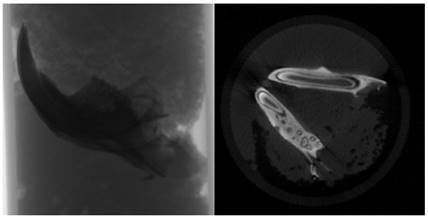

The specimens were meticulously prepared for scanning in a SkyScan 1174v2 computed tomography apparatus located in Kontich, Belgium (Bruker, Kontich, Belgium). Each sample underwent scanning with a 0.25 mm aluminum filter, utilizing a voltage of 50 kVp, a current of 800 μA, and a power setting of 40 W. The scan parameters were finely tuned to optimize an exposure time of 3500 ms, achieve a resolution of 1024x1304 pixels, and employ a zoom factor of 30.51 μm. Each sample underwent a complete 360-degree rotation with angular increments of 1.00 degrees, requiring approximately 50 minutes for completion (Figure 2).

Following the scanning procedure, a total of 361 raw images were generated in TIFF format, and these images were subjected to reconstruction utilizing the NRecon software (Version 1.6.10.2) (Bruker, Kontich, Belgium). Subsequently, approximately 800 sections were extracted in BMP format, as depicted in Figure 2. These sections were imported into the CTan software (Version 1.16.4.1+) (Bruker, Kontich, Belgium), facilitating the execution of densitometric and morphometric measurements to establish quantitative parameters and create visual models.

To delineate the boundaries of the region to be measured, a semi-automatic circular Region of Interest (ROI) was delineated in the horizontal plane on the image slices, as illustrated in Figure 3. A threshold value was ascertained within the histogram to differentiate between the voxels representing the sample under examination and those representing the surrounding air, as exemplified in Figure 4. Specifically, black voxels were assigned a value of 0, signifying the minimum intensity, while white voxels were assigned a value of 255, representing the maximum intensity.

Volumetric ratios were subsequently computed separately using the designated ROIs and the threshold data. To generate three-dimensional modeling images of the specimens, the data were transferred to the CTVol software (Version 2.3.2.0) (Bruker, Kontich, Belgium). A calcium hydroxyapatite (CaHA) calibration bar (phantom) was employed for the analysis, featuring calcium densities of 0.25 g/mm³ and 0.75 g/mm³. The CTAn software (Version 1.16.4.1+) (Bruker, Kontich, Belgium) was used to calculate measurements of bone mineral density (expressed in g/cm³) and bone volume (in cm³) within the specified region.

Raw image and sectional view.

Determination of ROI (Region of Interest) around the analysis area.

Determination of threshold value for the relevant field.